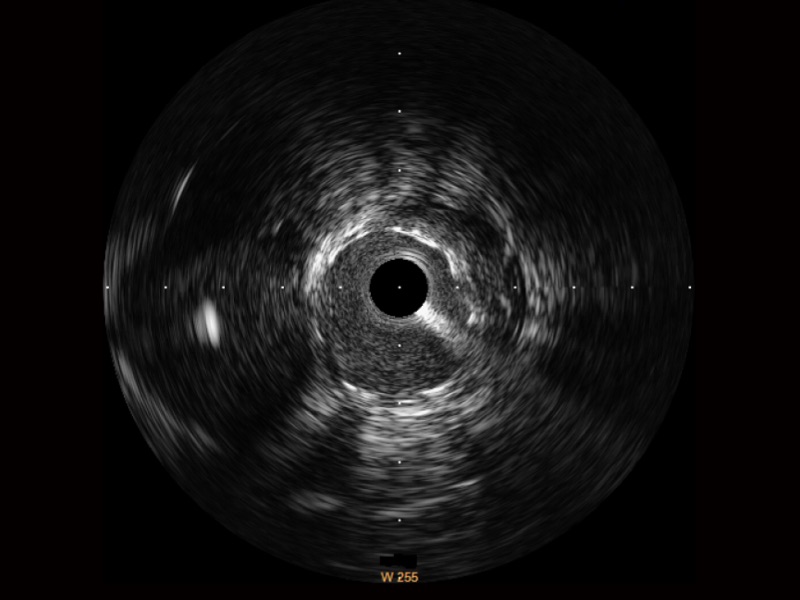

银河集团官网宽频IVUS图像

传统IVUS图像

对比传统IVUS导管成像,银河集团官网宽频IVUS图像的近场支架梁显影更细腻,远场中膜外血管仍清晰可辨,兼顾远中近,兼顾分辨力与穿透深度